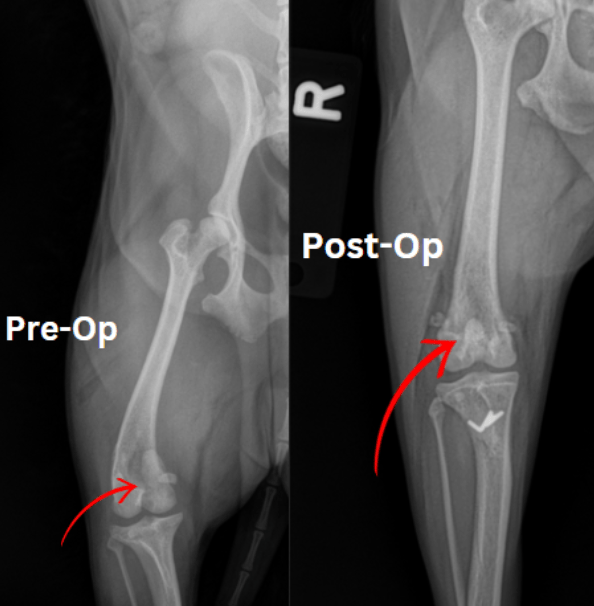

Femoral Head Ostectomy (FHO) is a surgical procedure commonly performed in dogs to address conditions such as hip dysplasia, hip fractures, or severe arthritis. The procedure involves removing the femoral head (the “ball” of the ball-and-socket hip joint), eliminating the source of pain and discomfort. Without the femoral head, the body forms a “false joint” within the surrounding muscles, providing pain relief and restoring mobility.